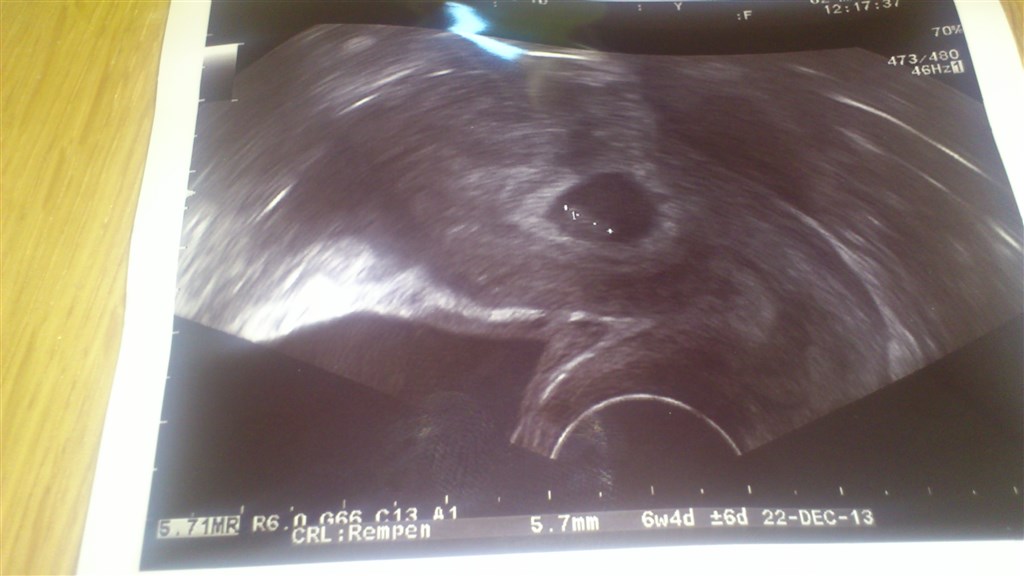

Ja så fik vi set den lille skumfidus

Efter mine beregninger (udfra sidste mens) skulle jeg være 7+0, skumfidus målte 5,7 mm tilsvarende 6+4, men som gynækologen sagde så kommer det jo helt an på hvornår jeg har haft ÆL og hvornår ægget har sat sig fast, så jeg skulle ikke være urolig!

Men det vigtigste: HJERTET SLÅR

Vedhæftede fotos (klik for at se i fuld størrelse)